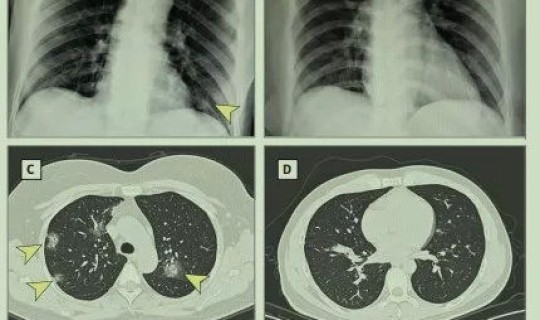

(图片来源于 *** 侵删)